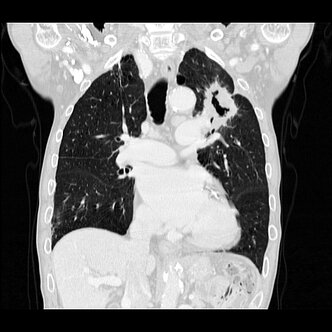

Alle wesentlichen diagnostischen und therapeutischen Verfahren zur Behandlung des Lungenkrebses sind an unserem Klinikum verfügbar z.B. PET-CT, MRT, Endosonographie (EBUS), Chemotherapie, Strahlentherapie, Operation, endoskopische Tumorabtragung und Stentimplantation, Behandlung von Tochtergeschwülsten (Metastasen) u.a. über Neuro- und Viszeralchirurgie oder interventionelle Radiologie.

Die modern ausgestattete Abteilung für Thoraxchirurgie am Städtischen Klinikum Dessau gewährleistet eine optimale Versorgung beim Lungenkrebs als auch bei anderen Erkrankungen im oder am Brustkorb. So werden z.B. Metastasen mit einem hocheffektiven Diodenlaser entfernt und Rippenfrakturen mit Titanklammern stabilisiert.

- Bronchialkarzinom – stadiengerechte Operation minimalinvasiv (z.B. VATS-Lobektomie) oder offen, inklusive erforderlicher Erweiterungen, sogenannter Manschettenresektionen

- Erkrankungen des Rippenfells (Pleuraerguss, Pleuraempyem, Pleuramesotheliom) wenn immer möglich minimal-invasiv - VATS